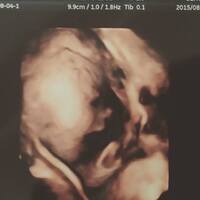

美容師です。 一児の父です。 写真は体内にいた頃の息子です。羊水プカプカ。 目下、ケミカルシャンプーラバーな美容師の息子は化学物質バリバリの羊水に浮かび、発射と同時にシャンプー臭を香らせていたのでしょうか? さて、昨日こんな記事を… 読まれてない方はまずご一読を。 そういった記事を読み、気になった文節に対…